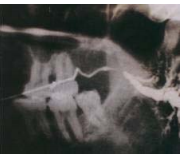

17. 如下圖之X光片所示,該唾液腺管呈現香腸狀之顯像,其最有可能之診斷為何?

(A)sialolithiasis (B)sialoadenitis (C)sialodochitis (D)sialocele